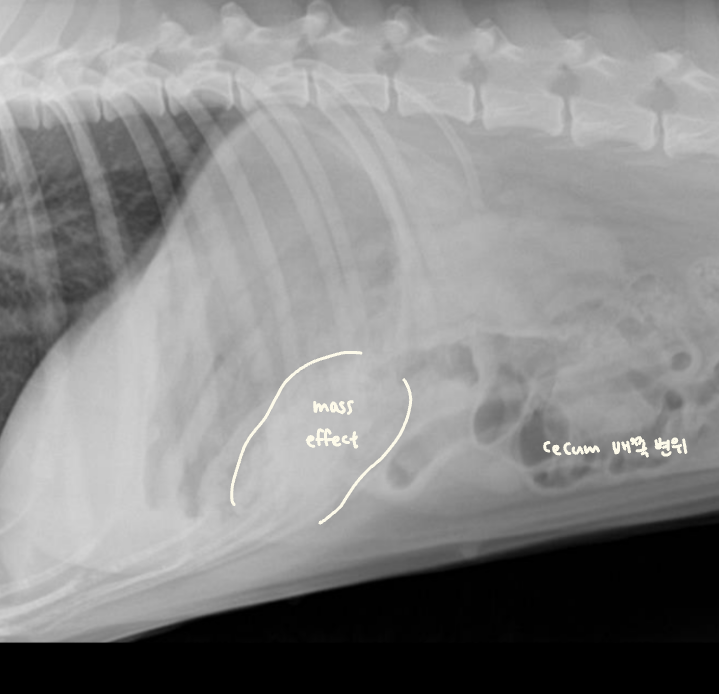

โ ๊ณจ๋ฐ๊ฐ ๋ด์์ ์๋ mass

- 4๊ฐ์์งธ ์ฌํ ๋ณ๋น + ์์๋ถ์ง, ์ฒด์ค ๊ฐ์, ๊ฐํ์ ๊ตฌํ ๋ก ๋ด์.

- Mass๊ฐ ๊ณจ๋ฐ๊ฐ ์์์ ์๋ผ๋ฉด ๊ฒฐ์ฅ๊ณผ ์๋๋ฅผ ๋ฐ์ด๋ด๊ณ , ์ ์ฑ ๋ณ๋น๋ฅผ ์ ๋ฐํจ.

- Leiomyoma๋ก ์ง๋จ๋จ.

โ ๋ด๊ฐ ์์ชฝ์์ ์๋ mass

- ๊ณจ๋ฐ๊ฐ๊ณผ ๋ฌ๋ฆฌ ๋ณต๊ฐ์๋ ์ฌ์ ๊ณต๊ฐ์ด ์์ด, ๋ด๊ฐ ๋ฐ๊นฅ์์ ์๊ธด mass๋ผ๋ฉด ๊ธธ์ ๋ง์ง ์์.

- ๊ทธ๋ฌ๋ ๋ด๊ฐ ์์ ์๊ธด mass๋ผ๋ฉด ๋ถ๋ณ์ด ๊ณ์ ์ถ์ ๋จ.

- ์กฐ์์ ๋ ์ผ์ ํ ๋๋น๋ก ํต๊ณผํ์ง ๋ชปํ๊ณ ๋งํ.